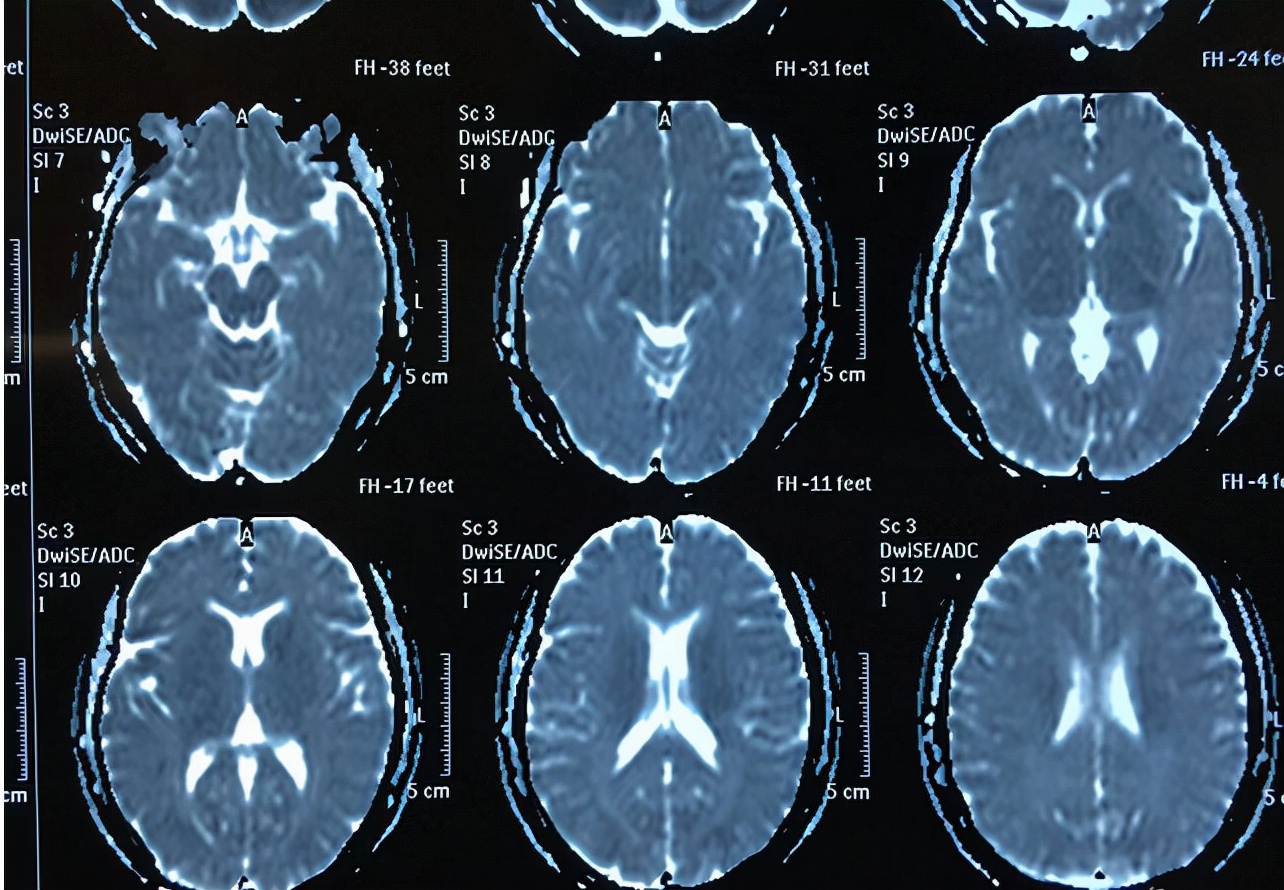

曾经碰到过这样一个小儿患者,是脑炎引发的癫痫,据家长反应,无缺氧难产病史、无高热惊厥史,就是在患儿六岁时曾患过病毒性脑炎,对于病毒性脑炎的具体诊疗过程不清楚,目前有两种发作形式,一种是愣神后出现自动症。第二是直接倒地,发作过后开始昏睡。白天、夜间均有频率发作,大概一个月6~7次,脑电图报告显示异常脑电图。目前患儿癫痫频发,#健康科普大赛#智力发育欠佳,不能正常语言沟通。

像这种脑炎导致癫痫的患者在治疗的时候是以药物治疗为主,主要是使用抑制患者神经兴奋的药物,抑制癫痫的异常放电状况,从而改善患者的发作状况,在给患者进行治疗的时候,应当做好脑电图的检查,根据检查结果来合理地用药,并且用药期间,患者也需要随时进行血药浓度检查,如果出现异常状况,需要及时的调整药物。